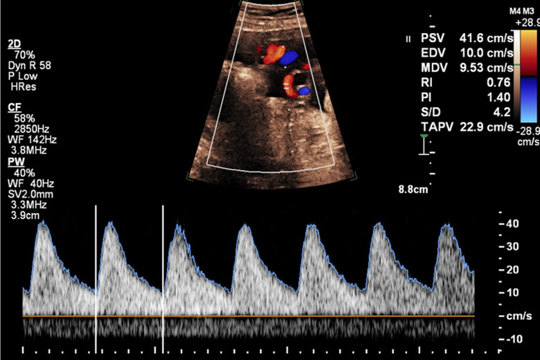

Doppler-Abschlusskurs

von 25. November bis 26. November 2022

Tübingen, Universitätsfrauenklinikum

A5/2022 - Dopplersonografie Kursreihe 2022